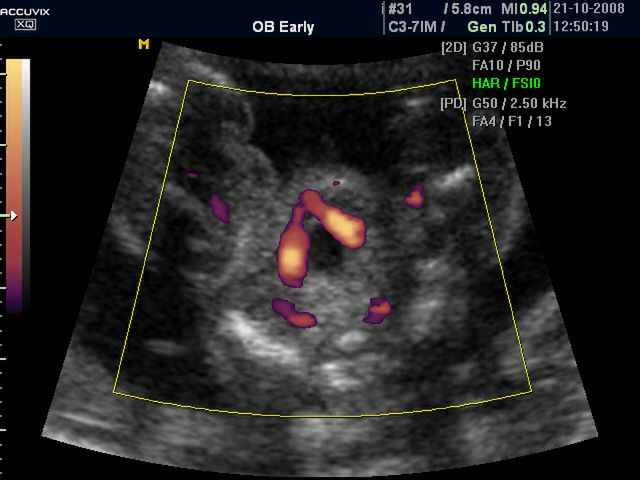

/ 10Zdjęcia płodu - pępowina w 29 tygodniu ciąży

Obraz

Płód w 29 tygodniu ciąży, na zdjęciu widoczne miejsce przyczepu pępowiny